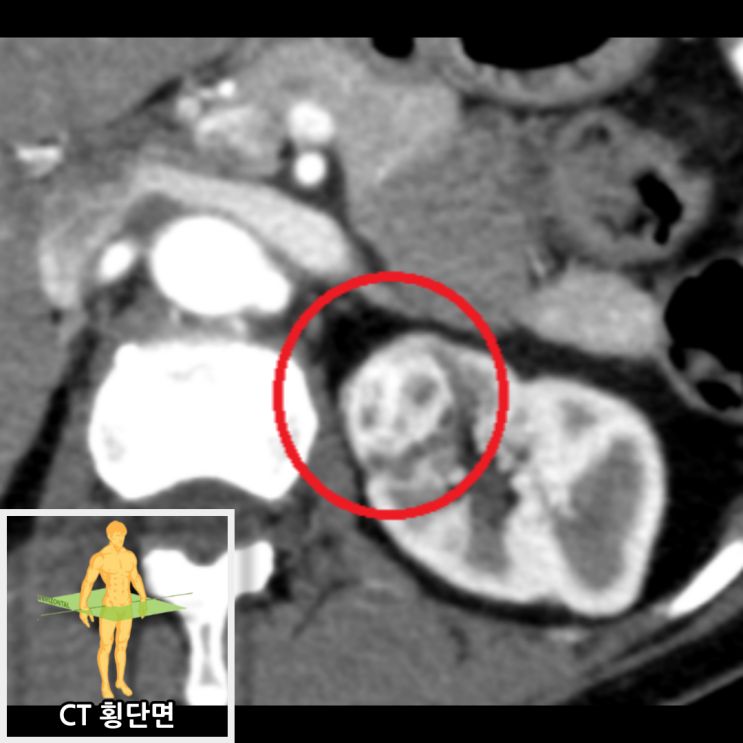

복부CT 횡단면 및 관상면 촬영에서 왼쪽 신장에 3.3cm 크기의 조영증강이 되는 병변이 발견되었습니다. 크기와 형태를 봤을 때 신장암 가능성을 배제할 수 없었습니다. 신장암이 요추(허리 척추) 근처에 위치하여 허리 신경을 압박하여 허리통증이 나타났을 것으로 사료됩니다.

• 복부CT 횡단면: 왼쪽 신장 병변 복부CT 횡단면: 왼쪽 신장 병변